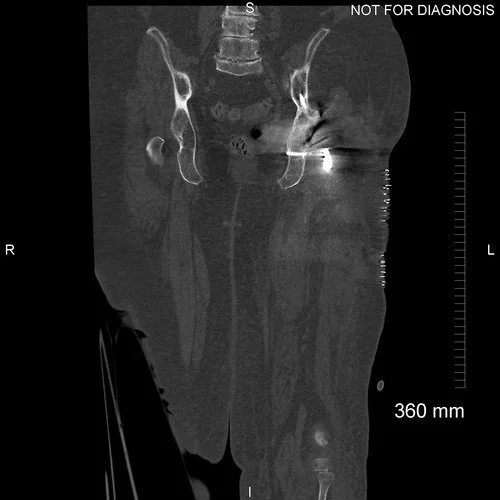

18 months prior to her referral she had developed swelling in her left thigh with fevers, malaise and night sweats. This was on the background of a left total hip replacement. DVT and malignancy were excluded. A CT scan showed a large collection around the left hip and a raised inflammatory marker: CRP = 198 mg/L (normal is less than 10).

Anteroposterior plain radiograph showing scalloping on the lateral aspect of the left proximal femur. Lytic areas are evident surrounding the cement mantle of the Exeter stem. The acetabular component has a constrained liner.